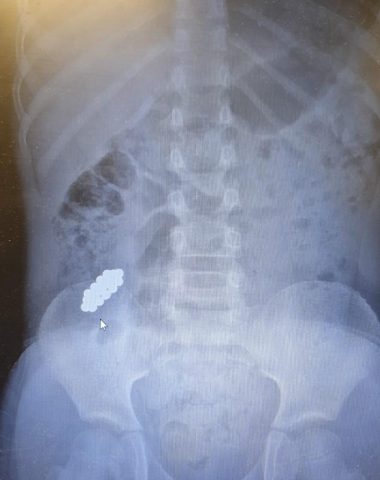

בן ה-8 הגיע למרכז רפואי מאיר מקבוצת כללית לאחר שבלע למעלה מ-20 מגנטים.

ד"ר אייל זיפמן, מנהל השירות לגסטרואנטרולוגיה ילדים מסביר: "בגלל ההבנה לגבי הנזק שמגנטים עלולים לחולל – והחשש מנקב במעי וזיהום בחלל הבטן, הוחלט לשלוח את הילד באופן מידי לצילום. בצילום נצפו המגנטים במעי הדק במקום שלא ניתן להגיע ללא ניתוח. הוחלט כי נעשה מעקב לבחון את מקומם ובשלב מסוים נמצא כי הם אינם מתקדמים לבד ויש לעשות קולונוסקופיה. המגנטים נמצאו במעי הגס והוצאו בהצלחה".